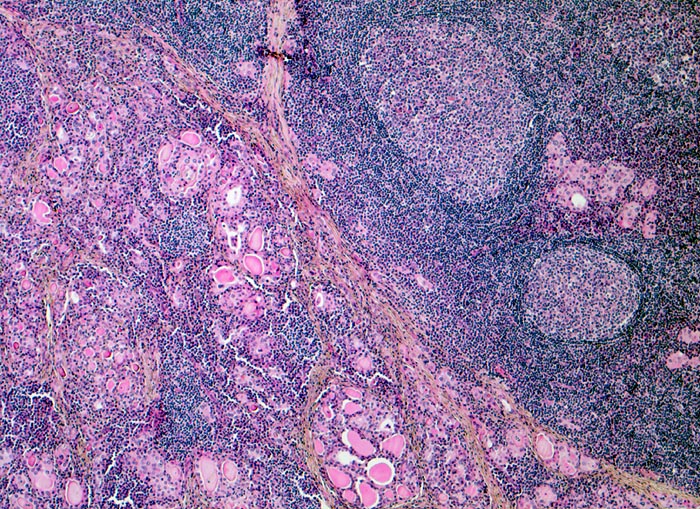

Mikrofollikuläres Schilddrüsenparenchym mit wenig Kolloid. Das Parenchym wird infiltriert und partiell zerstört durch ein dichtes lymphoides Entzündungsinfiltrat mit sekundären Lymphfollikeln. Stellenweise sind nur kleine Epithelinseln im Entzündungsinfiltrat stehengeblieben.

Die Patientin sucht den Hausarzt auf wegen leichter Schmerzen am Hals rechts. Symptome einer Schilddrüsendysfunktion sind auch auf gezielte Anfrage hin nicht vorhanden. Die Schilddrüse ist deutlich vergrössert. Die laborchemischen Untersuchungen ergeben eine pathologisch erhöhte Konzentration der Peroxidase- und Thyreoglobulin-Antikörper. Die Serumwerte für T4 und T3 sind normal, der Wert für TSH ist erhöht. Die Indikation zur Thyreoidektomie wird wegen der deutlichen Struma gestellt.